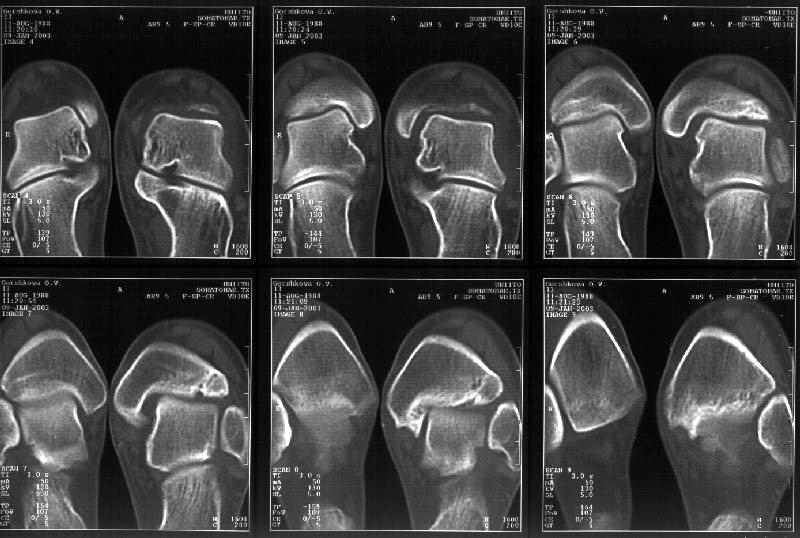

I attach CT of the affected ankle.

The CT seems to show residual triplane fx lines.

I wonder if this could have been a 4 part triplane with an intra-medial malleolar component as described by Von Laer JBJSA 67:687 1985 which was displaced by the im device?

John Early's suggestion of posterior medial malleolar debridement and possible medial malleolar repositioning for mortice narrowing is very interesting. You mention that the patient already has mediolateral instability. While it does push the talus laterally, it looks like the posterior medial malleolar fragment may be providing a congruent buttress against medial talar displacement. If that were removed and the mortise was not in some way narrowed - the mediolateral instability might increase.

I wonder if comparison CT cuts of the normal ankle and possibly 3D reconstruction/modeling might give a better understanding of the pathoanatomy.

Today the axial and frontal cuts were performed - attached.

The comparison coronal and axial CT show a tillaux component and a widened mortise which was probably first held open by the im device and then the malunion of posterior medial malleolar fragment - drawn into the joint by the deep deltoid talar attachment.

With posterior medial malleolar fx excision alone, mediolateral instability could increase. The wide mortise, a result of multiplanar fx deformity, needs to be narrowed - but how can this be reliably achieved? Perhaps a 3D model is needed ala

The CT scan does seem to identify malunion of the distal tibia, although the exact detail of the fragments and their displacement is not perfectly clear. We think it would be an ideal case for a 3D model.